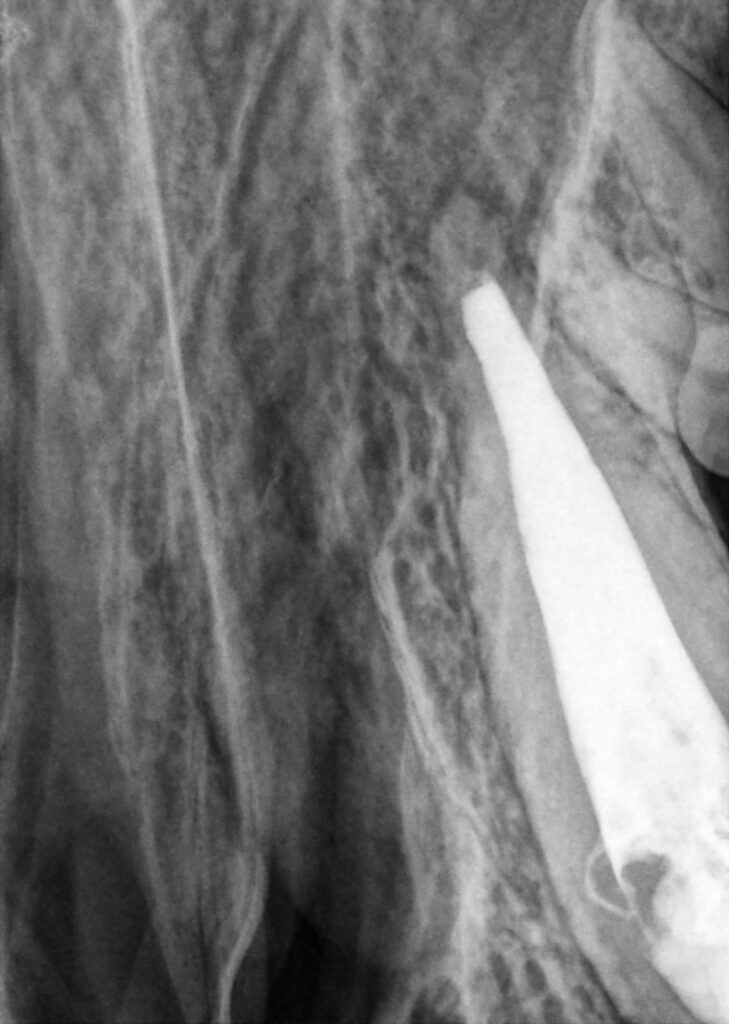

The patient was placed under general anaesthesia, and an exam and dental radiographs were performed (Figure 3). This confirmed the absence of a complete apex and the vertical root fracture.

The first step was to create a periodontal flap to restore the vertical root fracture and prevent leakage. Next, vital pulp therapy was performed (Figure 3) to protect the tooth and (hopefully) allow it to mature to the point of receiving root canal therapy in the future. The subgingival defect was restored with glass ionomer to allow for superior periodontal attachment. Finally, the flap was sutured (Figure 4).